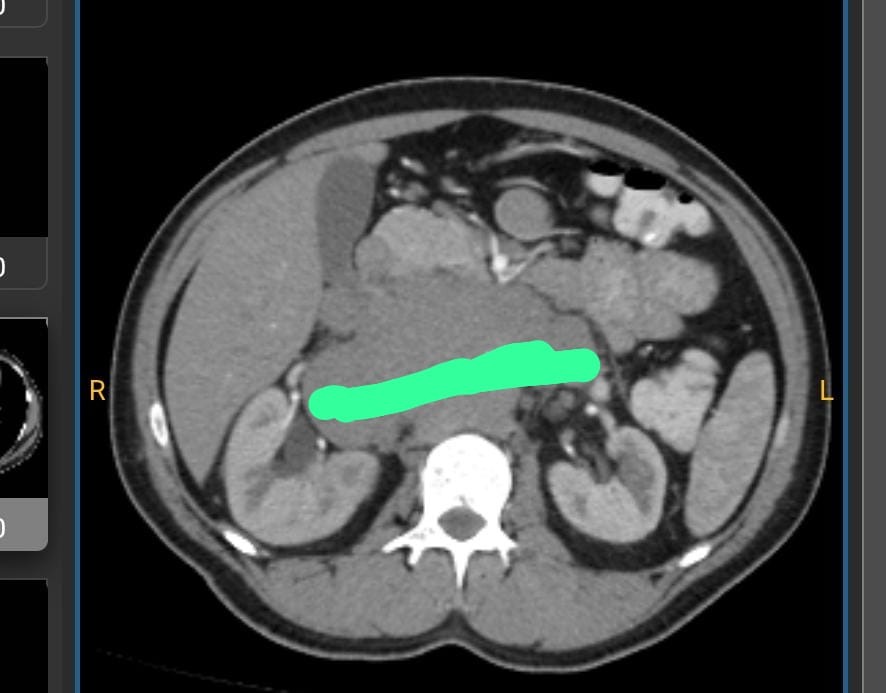

Hola mi nombre es Eduardo Tinoco, soy del municipio de Omealca, recientemente se me detecto un carcinoma que por su localización es inoperable ya que se encuentra localizado en mi aorta abdominal, sin embargo debo iniciar con un tratamiento de quimioterapias de manera urgente para poder reducir su tamaño y tener la esperanza de recuperarme pronto, este tratamiento por la rapidez que requiere deber ser en una institución particular, espero poder contar con tu apoyo y agradezco que me ayudes a compartir. Gracias, dios te bendiga.